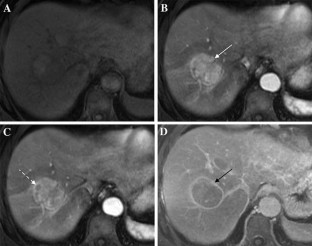

Fig. 1